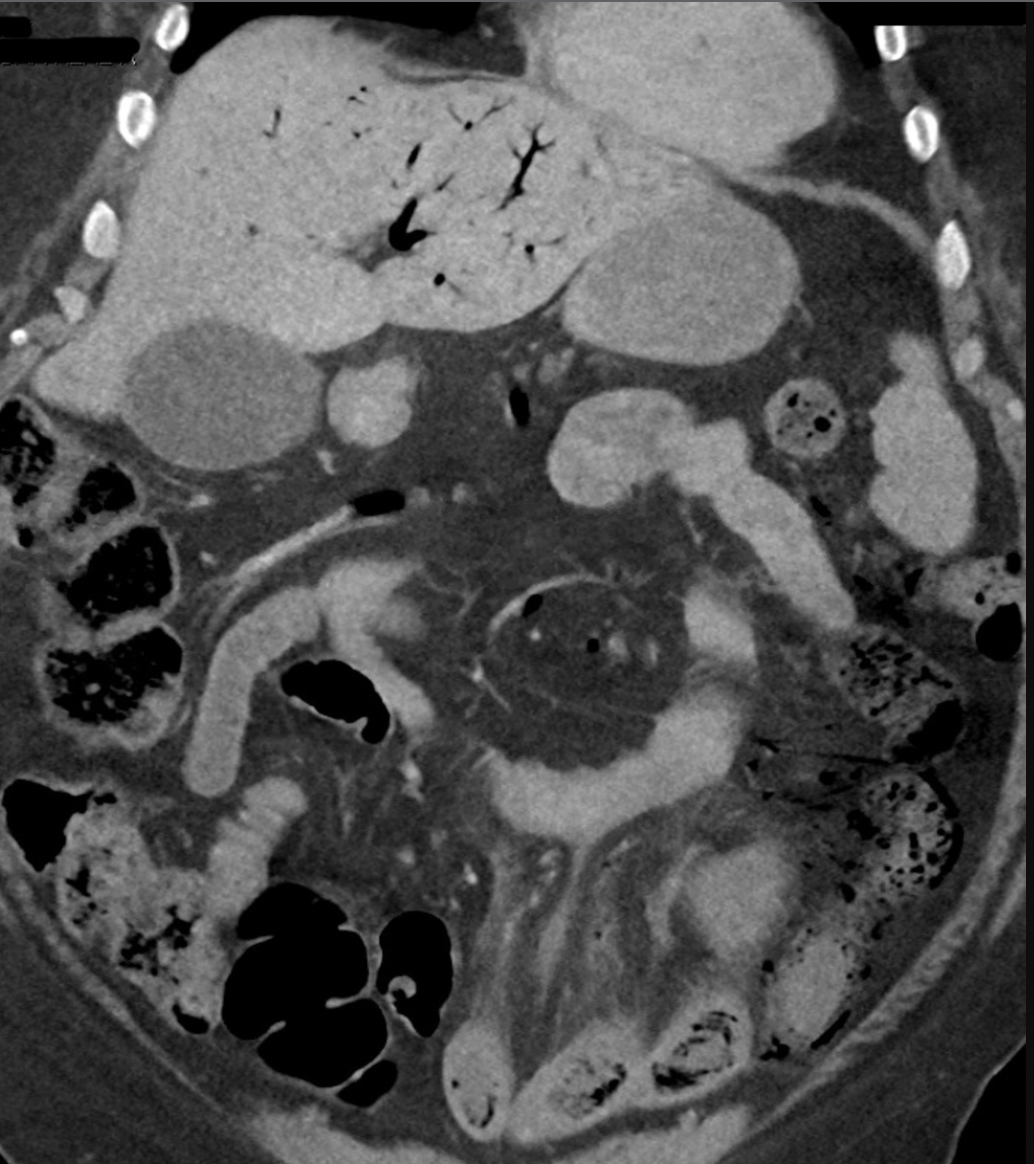

Severe abdominal pain in patient with CKD, HTN, DM

A

Acute mesenteric ischemia

LLQ fat stranding

portal venous gas